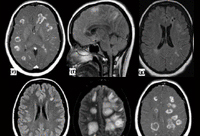

Células inflamatórias

Pesquisa sobre células neurais estuda como inibir processos inflamatórios no cérebro

(Texto: Instituto Biomédico)